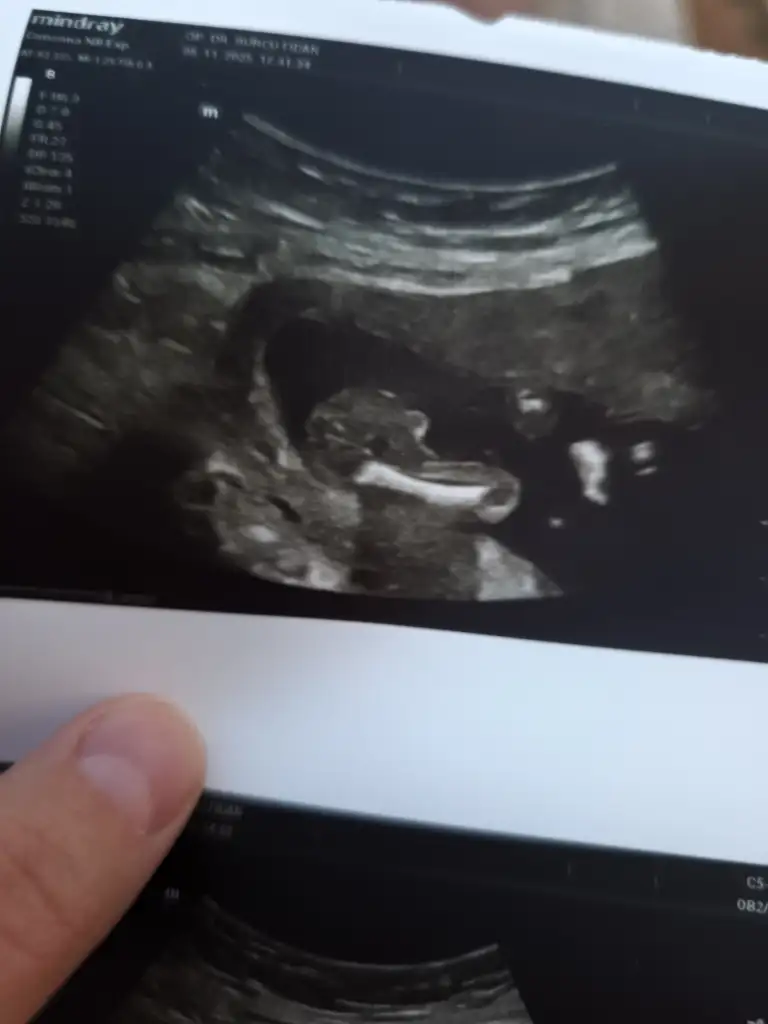

sizce kız mı erkek mi 16 hafta doktor bacağını açmıyor dedi bunu vereyim dedi